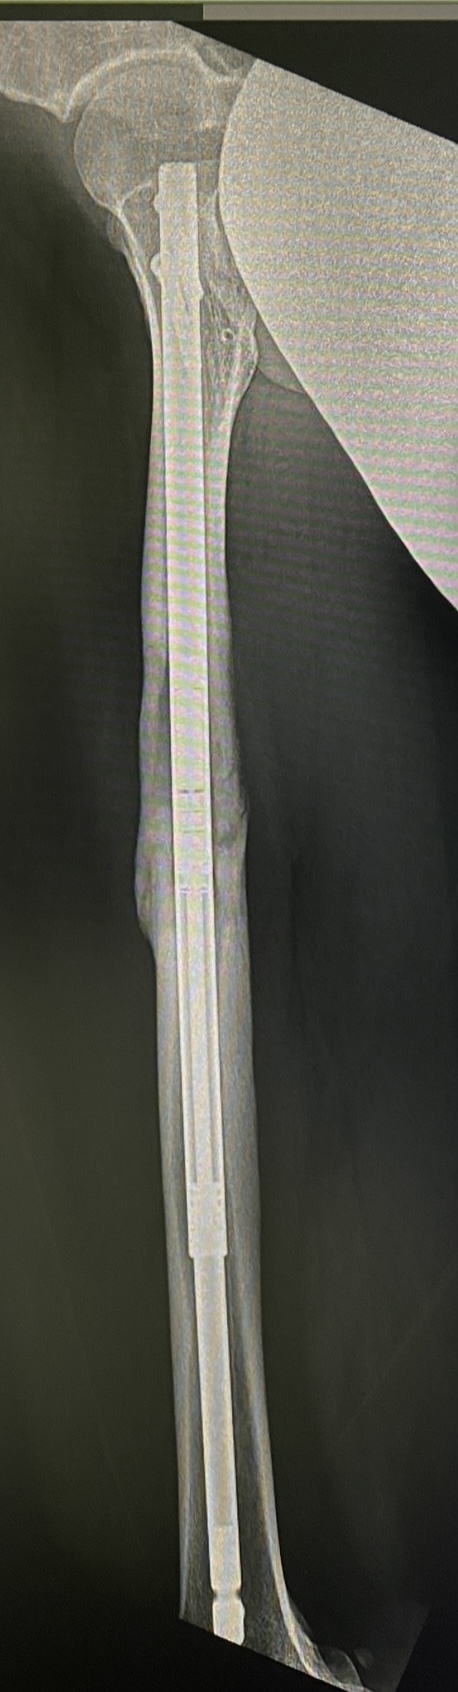

ตัวอย่างผู้ป่วยจริง ที่ได้รับการผ่าตัดเพิ่มความสูง ด้วย Precice ที่กระดูกต้นขา โดย นพ.ไตร พรหมแสง

Precice เป็นอุปกรณ์สำหรับใส่ในโพรงกลางกระดูก ใช้รีโมทส่งสัญญาณจากภายนอกสั่งให้อุปกรณ์ยืดออกวันละ 1 มม.

Precice nail (พรีใซส์ เนล) อุปกรณ์ที่ใส่ในโพรงกระดูก เพื่อยืดกระดูกออก

กระดูก femur ยืดได้สูงสุด 8 ซม. ยืดวันละ 1 มม. เริ่มยืดหลังผ่าตัดวันที่ 7 ใช้เวลายืดทั้งหมด 3 เดือน รอกระดูกติด (consolidate) อีก 3-5 เดือน จึงให้เดินได้โดยไม่ต้องใช้ไม้ค้ำยัน